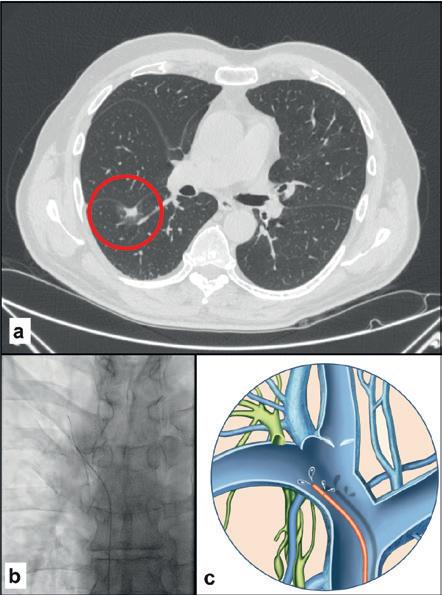

CASE ONE

Male, 76 years old

Spiculated lung nodule, 14mm (A) in the right lower lobe, ischaemic heart disease, respiratory failure. Liquid biopsy from the right subclavian vein (B, C) with a finding of pathogenic mutation CDH1. Surgical histological confirmation of minimally invasive adenocarcinoma.

this biomarker. The simplest method, investigated by us and confirmed by another research group, is to draw venous blood in proximity to the tumour site. Percutaneous venous catheterisation is part of the armamentarium of interventional radiologists and relies on their familiarity with navigating the vascular system under fluoroscopic guidance. Sampling sites can be chosen as dictated by the natural history of the disease, which includes both primary and metastatic sites.